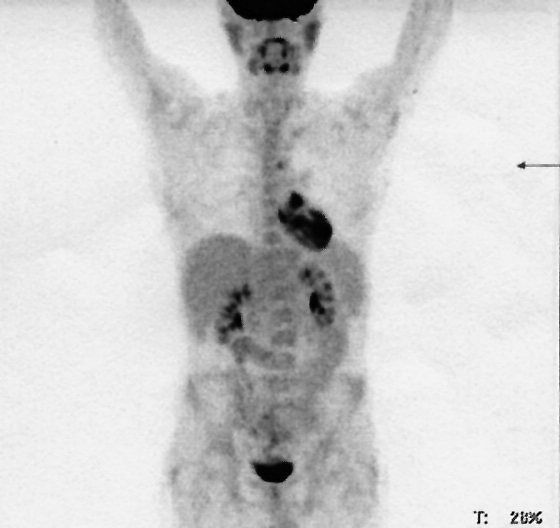

С июля по октябрь 2017 г. пациенту было проведено 6 циклов ХТ по программе ВЕАСОРР-14. Частичная ремиссия по данным КТ была достигнута после 2 циклов (ПЭТ-КТ не выполнялась по техническим причинам). На ПЭТ-КТ после 6 циклов определялась резидуальная активность в паратрахеальных лимфоузлах SUVmax до 3,4 (рис. 2). В ноябре – декабре 2017 г. в рамках комбинированного лечения была проведена лучевая терапия на средостение и правую надключичную область.

Рис. 2. ПЭТ-КТ после индукционной ХТ (резидуальная активность в паратрахеальных лимфоузлах).